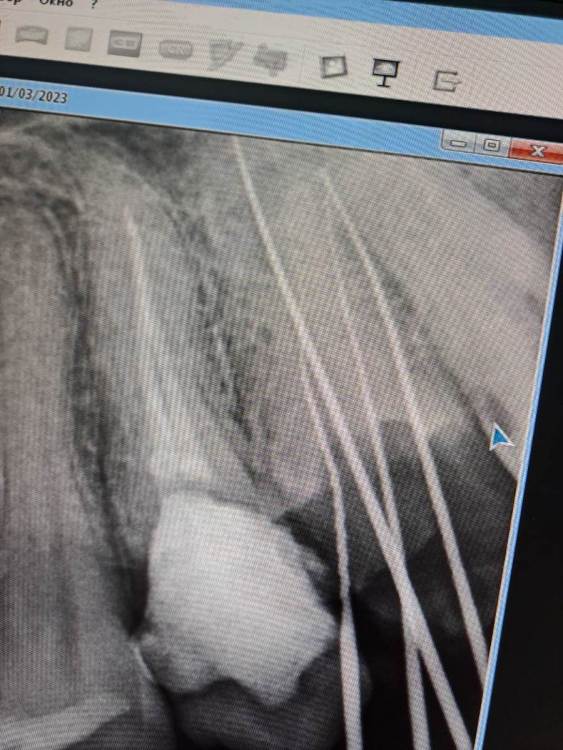

FISSMAN Опубликовано 7 апреля, 2023 Поделиться Опубликовано 7 апреля, 2023 Раньше постоянно воспалялся синусит, гнойная мокрота из пазух носа выходила в горло, постоянно слабость и потливость и иногда головные боли при переохлаждении. После удаления 2х зубов и лечении других зубков состояние улучшалось все лучше и лучше. После лечения двух последних зубов, лекарство в каналы и временная пломба, самочувствие стало норм и гнойная мокрота пропала, после заполнения каналов тоже было норм и желтая гнойная мокрота отсутствовала, далее меня направили к другому стоматологу ортопеду, от обточил 2 этих зубка для коронок и через несколько дней обратно появилась слабость и гнойная мокрота, уже около 15 сутк это продолжается, коронки ставить я пока отказался, потому что предпологаю что там могло что-то воспалится. Ничего не болит и не беспокоит, но и до лечения ничего не болело и не беспокоило и в самом начале лечения всех зубов ничего не болело из зубок и не беспокоило. На фото снимок прицельного рентгена этих двух зубок при лечении и после лечения каналов, сверху временная пломба. Не уверен что это из-за зубок как и не уверен в обратном. Посещал несколько ЛОР врачей, последний из них, то что самый квалифицированный поставил предварительный диагноз ринит алергический, направил на анализы, там обнаружился аллерген. Ссылка на комментарий

FISSMAN Опубликовано 8 апреля, 2023 Автор Поделиться Опубликовано 8 апреля, 2023 3 часа назад, IvanK сказал: пазухи выглядят хорошо 18,28 надо удалять 16,17 лечить 15 - периодонтит - может быть "виновником торжества" (причиной синусита, если обострится) 25, 26 - перелечивание и протезирование если это старый снимок, то имеет смысл делать новый.. Спасибо! 18,28 - удалены 16,17 - пролечены 15 - пролечен (ставили лекарство и временную пломбу, потом постоянную) 25, 26 - лечатся... Ставили лекарство в каналы зубов, мое самочувствие улучшилось, пропала гнойная мокрота из горла. Потом запломбировали каналы, мое состояние было норм, гноя не было. Через 4 сутки другой стоматолог ортопед обточили эти 2 зуба до корней для установки на них коронок, взял замеры и через несколько дней у меня обратно появилась слабость, желтая гнойная мокрота, потливость и ныла поясница, как обычно при воспалении синуситов (она ноет параллельно). Коронки ставить в таком состоянии отказался, потому что возможно эти каналы воспалились, но не уверен что это из-за зубов... Уже прошло около 18 суток примерно, состояние +- такое же, слабость и мокрота. Отмечу что в самом начале лечения всех зубов (несколько месяцев назад) слабость была намного сильнее и при этом часто сильно болел лоб из-за отека в пазухе, сейчас не болит. Раньше в 10 случаях из 10, после того как я выйду на улицу зимой и погуляю там часа 2,3ч. у меня к вечеру начинал болеть лоб и боль усиливалась, после того как сниму отек боль проходила и последующие несколько дней чувствовал слабость, гнойный запах носом. Сейчас такого нет, симптомы менее выражены. Сейчас пойду в другую стоматологическую клинику, смотреть эти два зубка. Стоматолог что лечил зубы мне понравился, вроде норм. лечит. но он сейчас не отвечает на звонки, х3 может ему не понравилось что я не пришел ставить коронки... Или ему не интересны сложности и он больше предпочитает лечить молодых чикс))) Еще вопрос по поводу КТ, когда его можно сделать ? Стоматолог что лечил мне зубы сказал воспаления или отечность на деснах которые у меня были, не уйдут даже через несколько месяцев и будут отображаться если я сразу после лечения сделаю КТ. Ссылка на комментарий